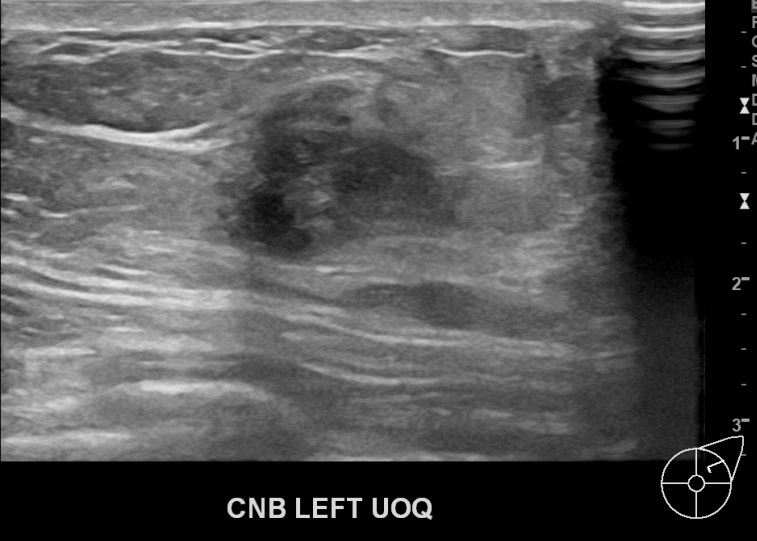

외부검사상 이상소견으로 내원하신 60대 여성분으로 좌측유방 조직검사후

유방암 진단되셨읍니다.빠른쾌유 바랍니다